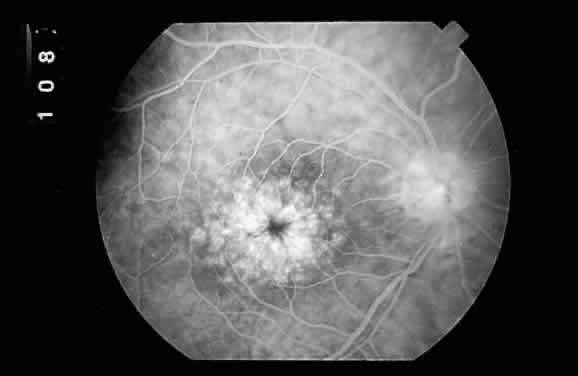

in the region of the ciliary body.  Fig. 16. Fundus photograph of a disciform macular scar, white because of fibrosis

and atrophy of the pigment epithelium. A broad, C-shaped, fresh hemorrhage

within the sensory retina surrounds it. Fig. 16. Fundus photograph of a disciform macular scar, white because of fibrosis

and atrophy of the pigment epithelium. A broad, C-shaped, fresh hemorrhage

within the sensory retina surrounds it.